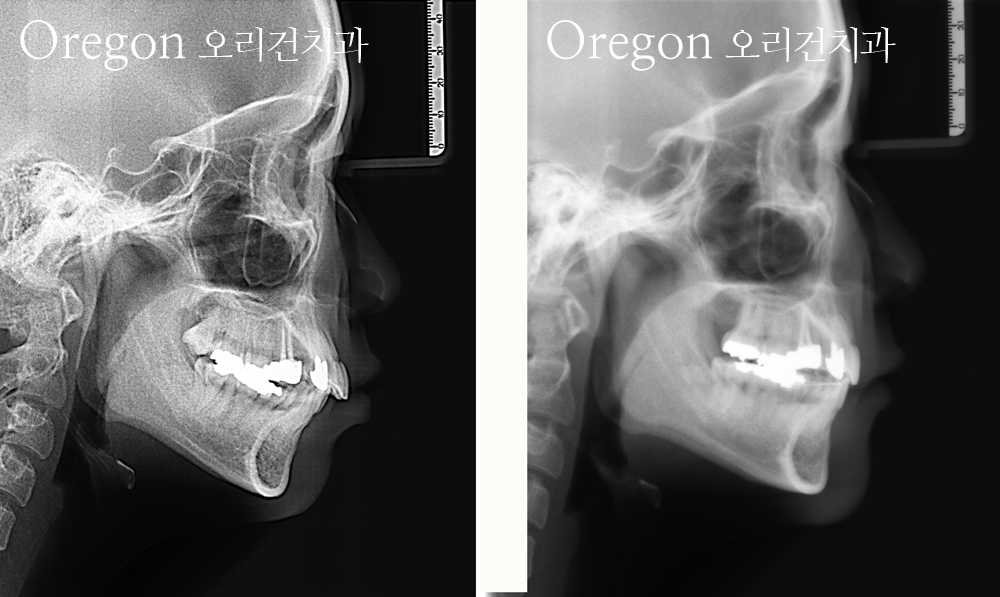

아래의 사례들은 치아를 발치하고 교정한 후에 내원한 분들로 추가적인 발치없이

전체 치열을 뒤로 넣어주어 심미적으로 만족하게 돌출입 재교정을 한 경우입니다.